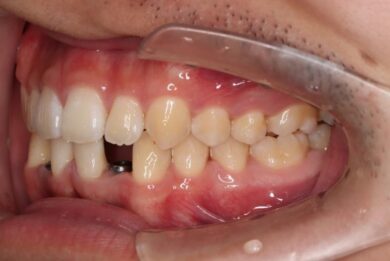

インプラントは世界シェアNo,1の「ストローマン」インプラントを採用。若年者の方も安心して長期的にお使いできるよう配慮しています。

• インビザライン終了後、インプラント2本埋入2週間後